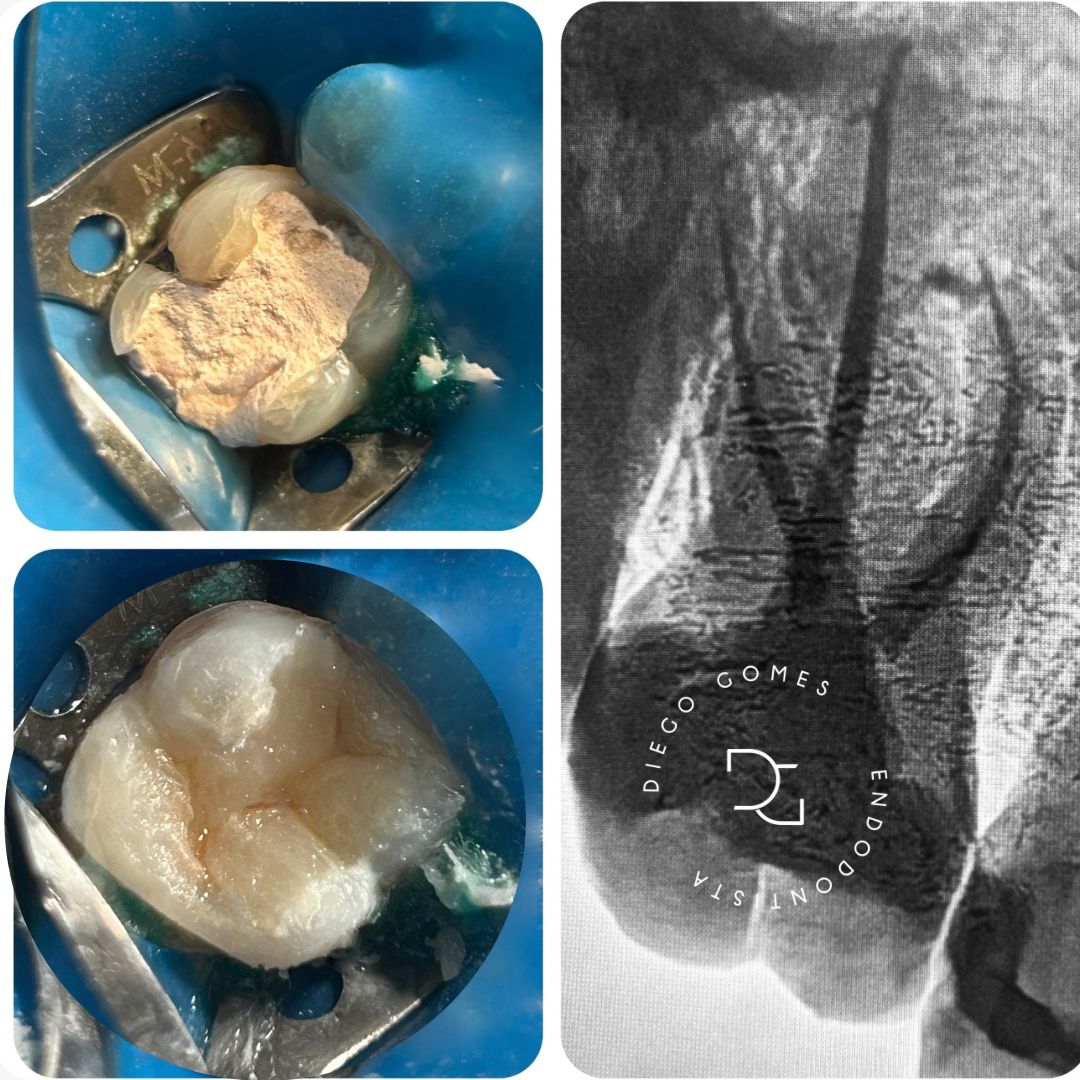

Seu trabalho é baseado em diagnóstico clínico e radiográfico criterioso, uso de tecnologia e atenção individualizada. Com uma abordagem técnica precisa e humanizada, realiza o tratamento completo, incluindo procedimentos preventivos, tratamento de canal e a reabilitação do dente, permitindo que ele volte à sua função por meio de restauração em resina composta ou coroa em cerâmica e, quando necessário, pino de fibra de vidro, sempre com foco na qualidade de vida e no bem-estar.

● Capeamento pulpar direto e indireto com uso de biocerâmicos

● Confecção de núcleo de fibra de vidro (pino) Se você está sentindo dor, sensibilidade prolongada ou foi diagnosticado com a necessidade de um tratamento de canal, entre em contato.